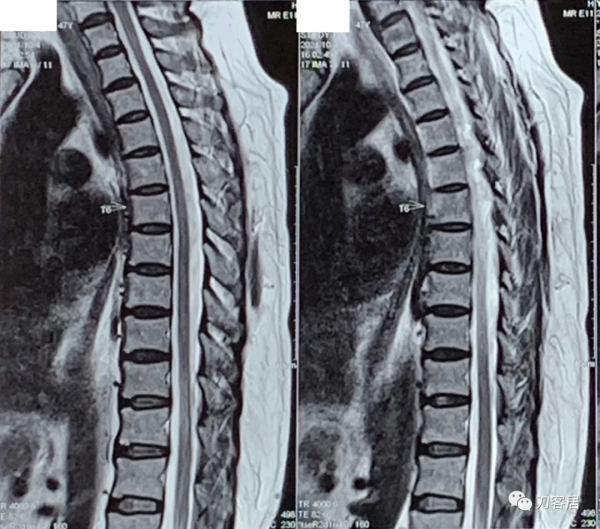

自帶腰椎MRI未見嚴重的椎間盤突出及椎管狹窄。自帶髖關節MRI未見異常,自帶胸椎MRI未見異常。自帶頸椎MRI提示頸4-5,頸5-6椎間盤突出,頸椎失穩。

圖9. 20211004頸椎MRI矢狀面T2相及橫截面。提示頸4-5,頸5-6,頸6-7椎間盤突出,椎管狹窄,脊髓訊號改變。

圖10. 20211004頸椎MRI矢狀面T2相及橫截面。提示頸4-5,頸5-6,頸6-7椎間盤突出,椎管狹窄,脊髓訊號改變。

圖11. 20211004頸椎MRI矢狀面T2相,提示頸4-5,頸5-6,頸6-7椎間盤突出,椎管狹窄,脊髓訊號改變。

圖12. 20211004頸椎MRI矢狀面T2相,提示頸4-5,頸5-6椎間盤突出,椎管狹窄,脊髓訊號改變。此兩間隙應該是責任間隙。也應存在頸4-5,頸5-6之間的不穩。

圖13. 20211004頸椎MRI矢狀面T1相,提示頸4-5,頸5-6椎間盤突出,椎管狹窄,脊髓訊號改變。此兩間隙應該是責任間隙。也應存在頸4-5,頸5-6之間的不穩。

圖14. 20211004頸椎MRI矢狀面T1相,提示頸4-5,頸5-6椎間盤突出,椎管狹窄,脊髓訊號改變。此兩間隙應該是責任間隙。也應存在頸4-5,頸5-6之間的不穩。